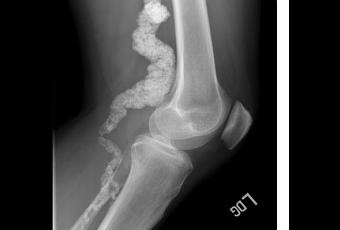

L'IRM et les rayons X ont montré que les membres des 2 familles avaient tous une accumulation de calcium dans les artères dans la moitié inférieure de leur corps, mais pas autour du cœur. Dans l'une des familles, 5 frères et sœurs -mais aucun des deux parents- étaient affectés par le trouble. Les chercheurs ont soupçonné que les symptômes pouvaient être liés à un variant génétique récessif.

Source : NIH «Rare Artery Disease Linked to Gene Variant » (Visuel NIH courtesy of NHGRI « Une radiographie du genou d'un patient avec ACDC, montrant l'accumulation de calcium dans l'artère »)